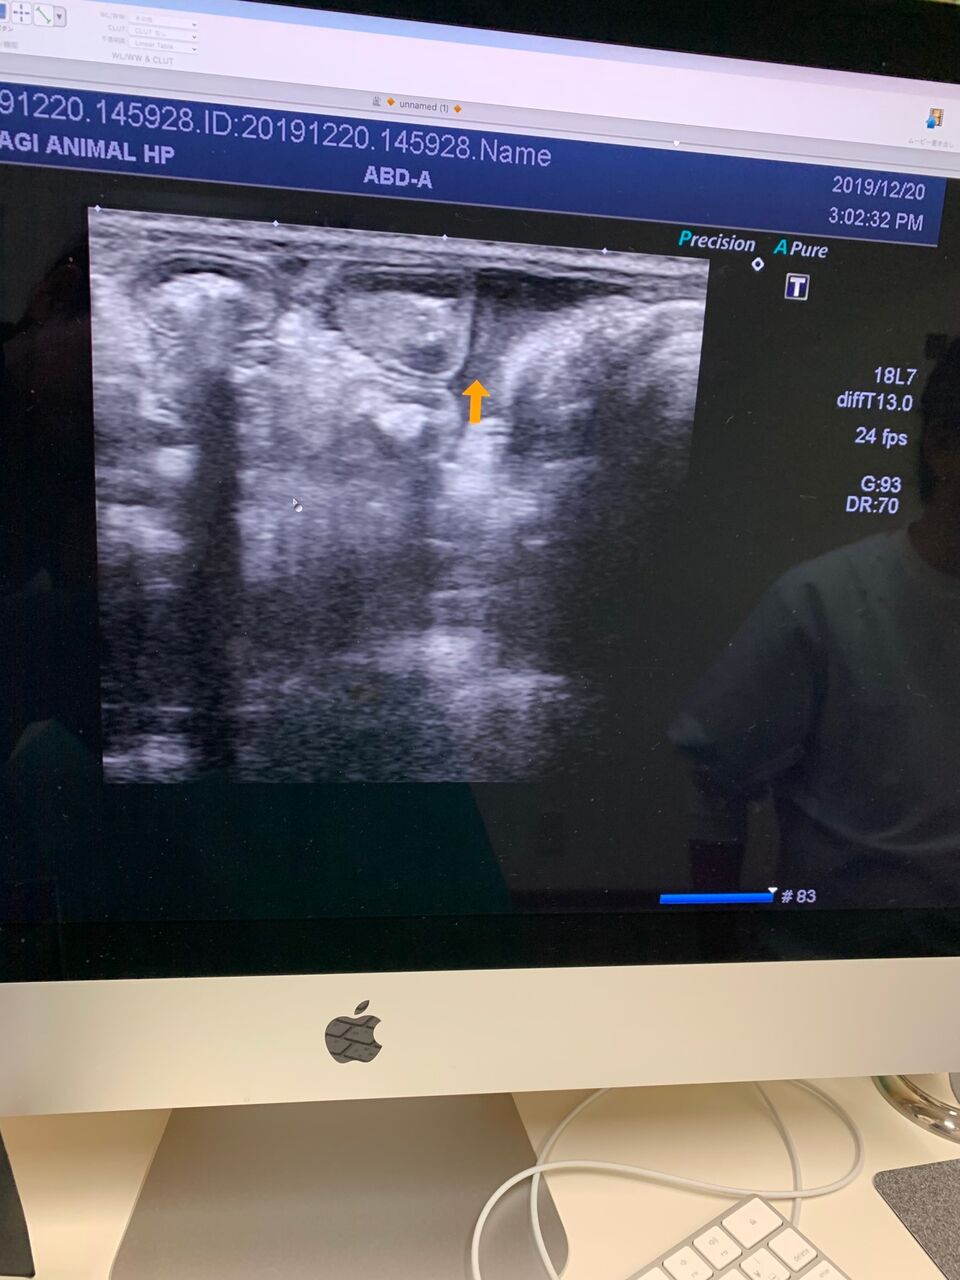

でも、微熱と言うか、40度ぐらいの熱が続くカカオは、若干、腹水もみられ、

最悪な事にFIPの診断が下されてしまいました。。。